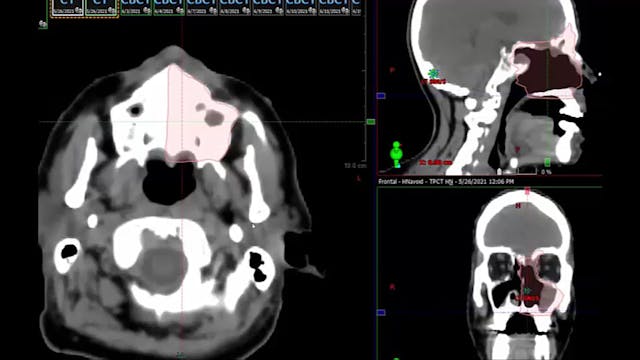

06/28/2021 Dr. David Sher - Radiation...

malignant melanoma, treatment fields in the sinonasal area, dose, HPV positive malignancy, positive margin